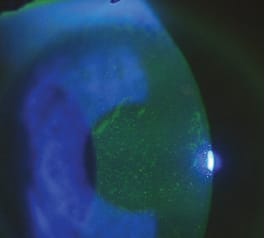

The patient's presenting visual acuities with contact lenses were OD 20/30 and OS 20/60. External examination revealed bilateral pannus spreading downward from the anterior limbus; vascularization was much more extensive in the left eye, extending close to the visual axis (Figures 2 and 3). After removing the contact lenses, we noted a coarse punctate keratitis that was more pronounced in the left eye (Figure 4). We also found significant superior limbal edema OD and OS.

Figure 3. Patient's pannus OS.

Figure 4. Patient's punctate keratitis.